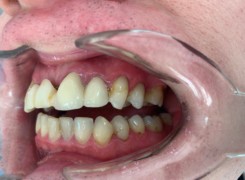

Pan Ryszard trafił do Naszego Gabinetu z jasno sprecyzowanym oczekiwaniem. Miał 84 lata i chciał odzyskać możliwość swobodnego spożywania posiłków oraz poprawienia sobie komfortu życia a także prosił aby przywrócić mu piękny uśmiech jakim cieszył się przed laty. Już na początku pierwszej rozmowy zastrzegł, że interesuje go wyłączenie rozwiązanie uzupełnieniem protetycznym stałym. Nie miał zamiaru użytkować żadnych protez ruchomych. Mając na uwadze powyższe wykonaliśmy Panu Ryszardowi zdjęcie pantomograficzne oraz badanie tomograficzne szczęki i żuchwy na postawie których zapanowywaliśmy Pacjentowi optymalne rozwiązanie – stałe uzupełnienie protetyczne w postaci 28 koron cyrkonowych zamontowanych do dwóch belek cyrkonowych które będą przymocowane do 16 implantów w konfiguracji 8 wszczepów w szczęcie 8 w żuchwie. Po omówieniu powyższego planu przystąpiliśmy do Wspólnej pracy której efekty w poszczególnych etapach prezentujemy poniżej.